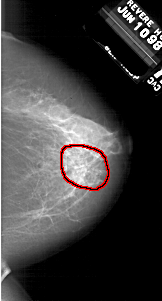

A_1847_1.RIGHT_MLO

FILE: A_1847_1.RIGHT_MLO.OVERLAY

TOTAL_ABNORMALITIES 1

ABNORMALITY 1

LESION_TYPE MASS SHAPE ARCHITECTURAL_DISTORTION MARGINS SPICULATED

ASSESSMENT 4

SUBTLETY 4

PATHOLOGY BENIGN

TOTAL_OUTLINES 1

BOUNDARY